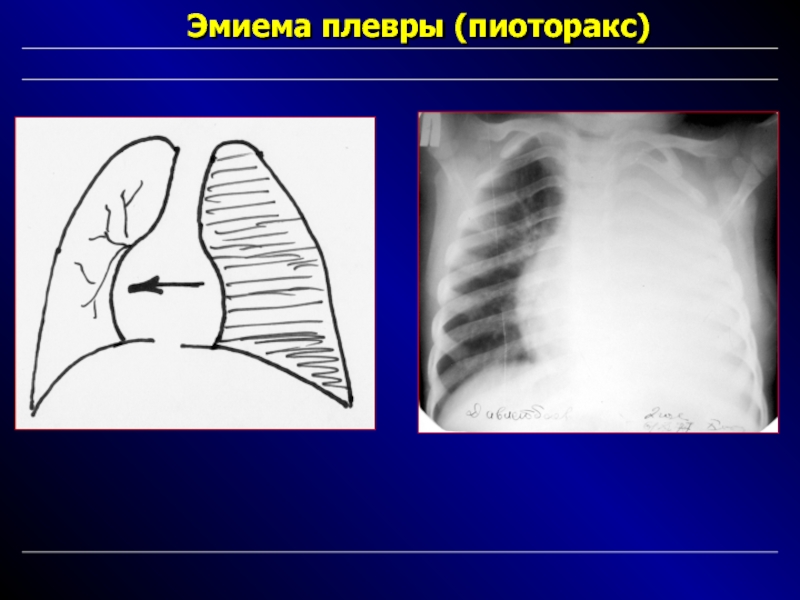

Бактериальная деструкция легких у детей презентация - 88 фото